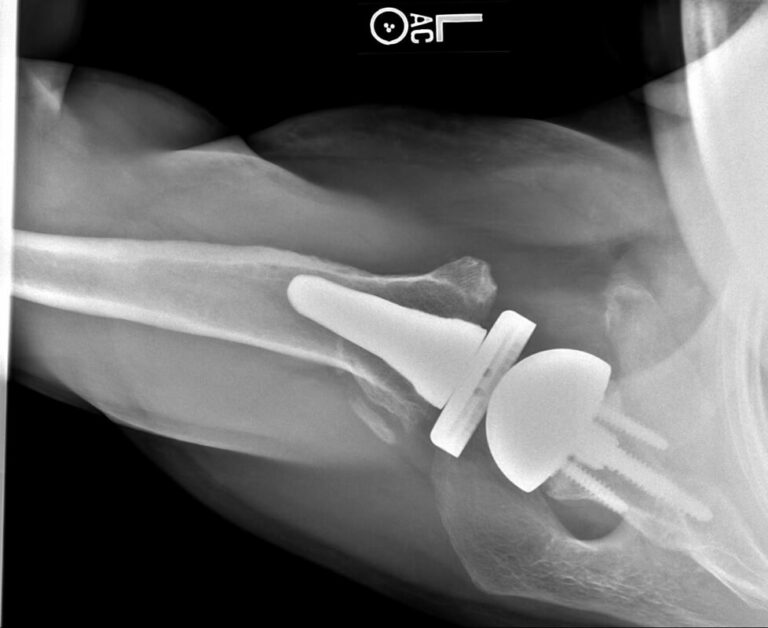

American Shoulder and Elbow Surgeons > Stryker/Wright/Tornier, Perforrm

Stryker/Wright/Tornier, Perforrm